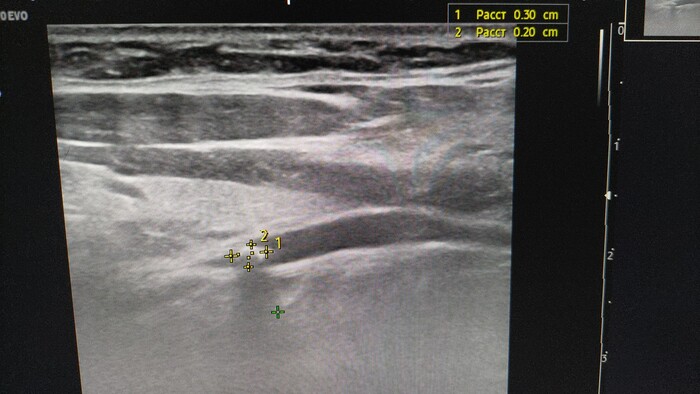

Вчера по дежурству привезли бабушку с болями в животе справа. Скорая помощь, видя и зная о том, что была аппендэктомия, ставит такой вот диагноз.. На моё справедливое возмущение, было сказано: «доктор, а вы что не знали что у половины из тех кого оперируют, он вырастает опять?»..